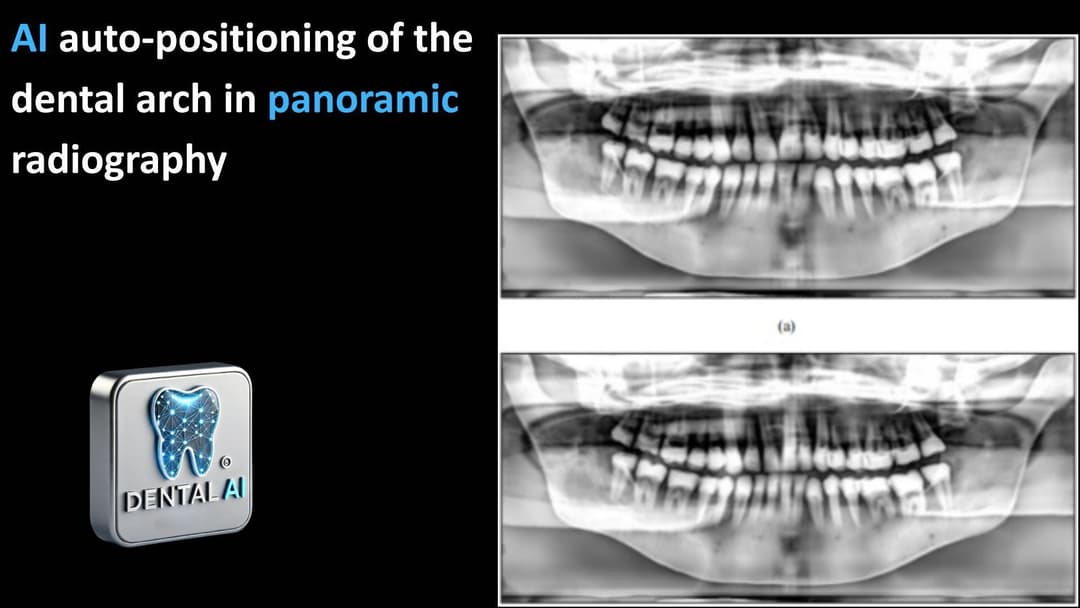

A Convolutional Neural NetworkBased AutoPositioning Method for Dental Arch in Rotational Panoramic Radiography Authors: Xin Du, Yi Chen, Jun Zhao, Yan Xi Summary Dental panoramic radiography (DPR) is...